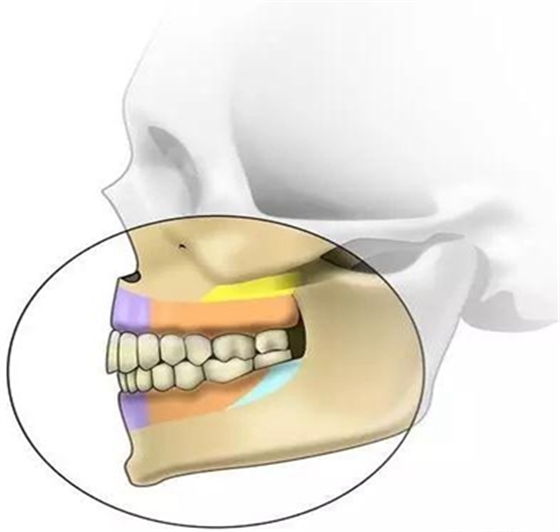

根據(jù)骨類型,骨密度,牙根間距、粘膜厚度不同,把上下頜分為不同區(qū)域,分別用紫橙藍(lán)黃四種顏色標(biāo)記,這些區(qū)域就是傳統(tǒng)的可植入部位,每個(gè)部位所選擇的支抗釘也相應(yīng)會(huì)有所差異

顴牙槽嵴(成人多在67之間,未成年多在56之間或6上方,根據(jù)CT確定)

危險(xiǎn)因素:此處植入容易穿破上頜竇底,植入角度需注意;骨質(zhì)較為堅(jiān)硬,支抗釘易折斷

植入位置和角度:在不滑脫的基礎(chǔ)上越平行于骨面越安全。要根據(jù)顴牙槽嵴的斜度決定植入角度,為避免滑脫,

可先垂直于骨面植入,在調(diào)整方向斜向上,一般植入角度向牙合面旋轉(zhuǎn)60°-70°

大?。河捎诖颂幑琴|(zhì)堅(jiān)硬,宜用10×2.0mm,且支抗釘尖端應(yīng)有切削頭設(shè)計(jì),以切削骨碎屑,利于植入腭側(cè)牙根之間